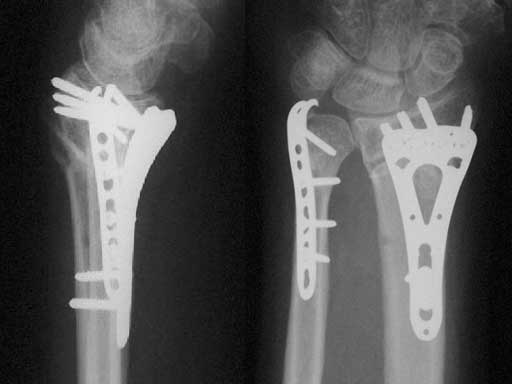

Fig 2ab AP and lateral x-rays 4 months after ORIF of a segmental unstable fracture of the distal ulna including basistyloid avulsion and extraarticular fracture of the distal radius.